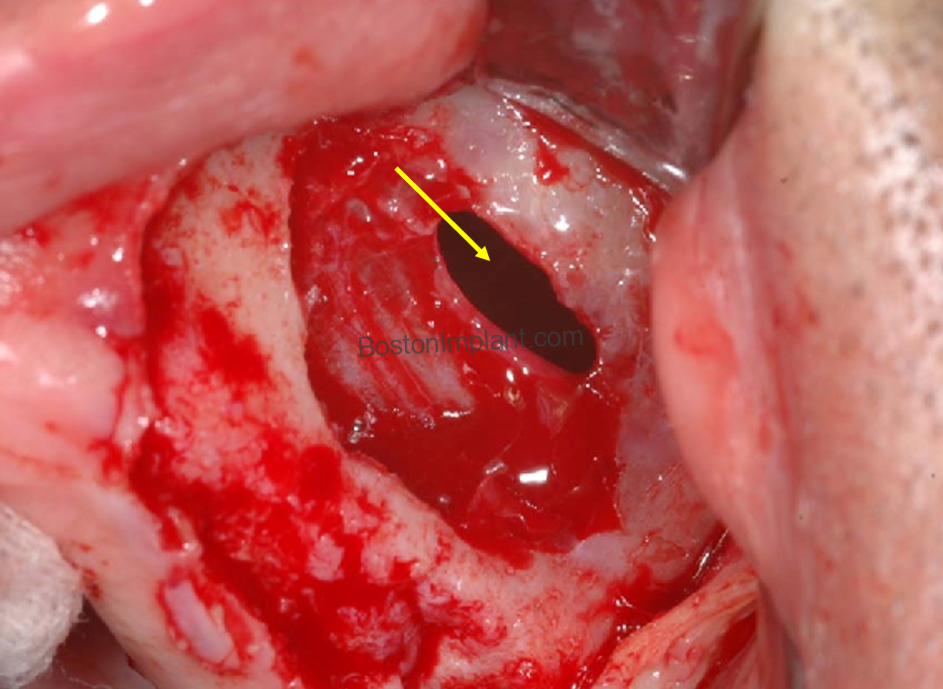

1. Schneiderian Membrane Perforation

The most common complication is a small tear in the Schneiderian membrane, which is the thin lining of the sinus. To visualize its fragility, think of the thin inner membrane of an eggshell; it is extremely delicate and requires expert manipulation.

- The Risk: This occurs in roughly 20% to 25% of cases. It is more common in patients with a “thin” membrane phenotype or those with internal bony walls called septa.

- Management: If a small tear occurs, specialized collagen membranes or fibrin adhesives are utilized to seal the area, ensuring the graft remains protected and successful.